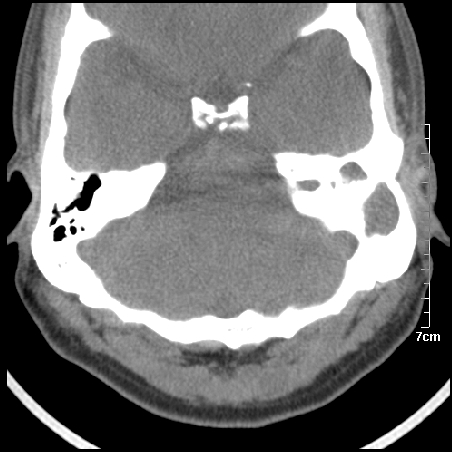

病例2

m/27

左中耳乳突炎合并胆脂瘤形成